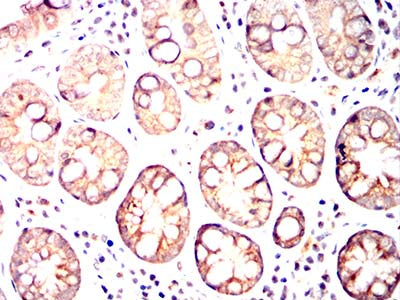

Immunohistochemical analysis of paraffin-embedded rat kidney tissues using MRP3 mouse mAb with DAB staining.